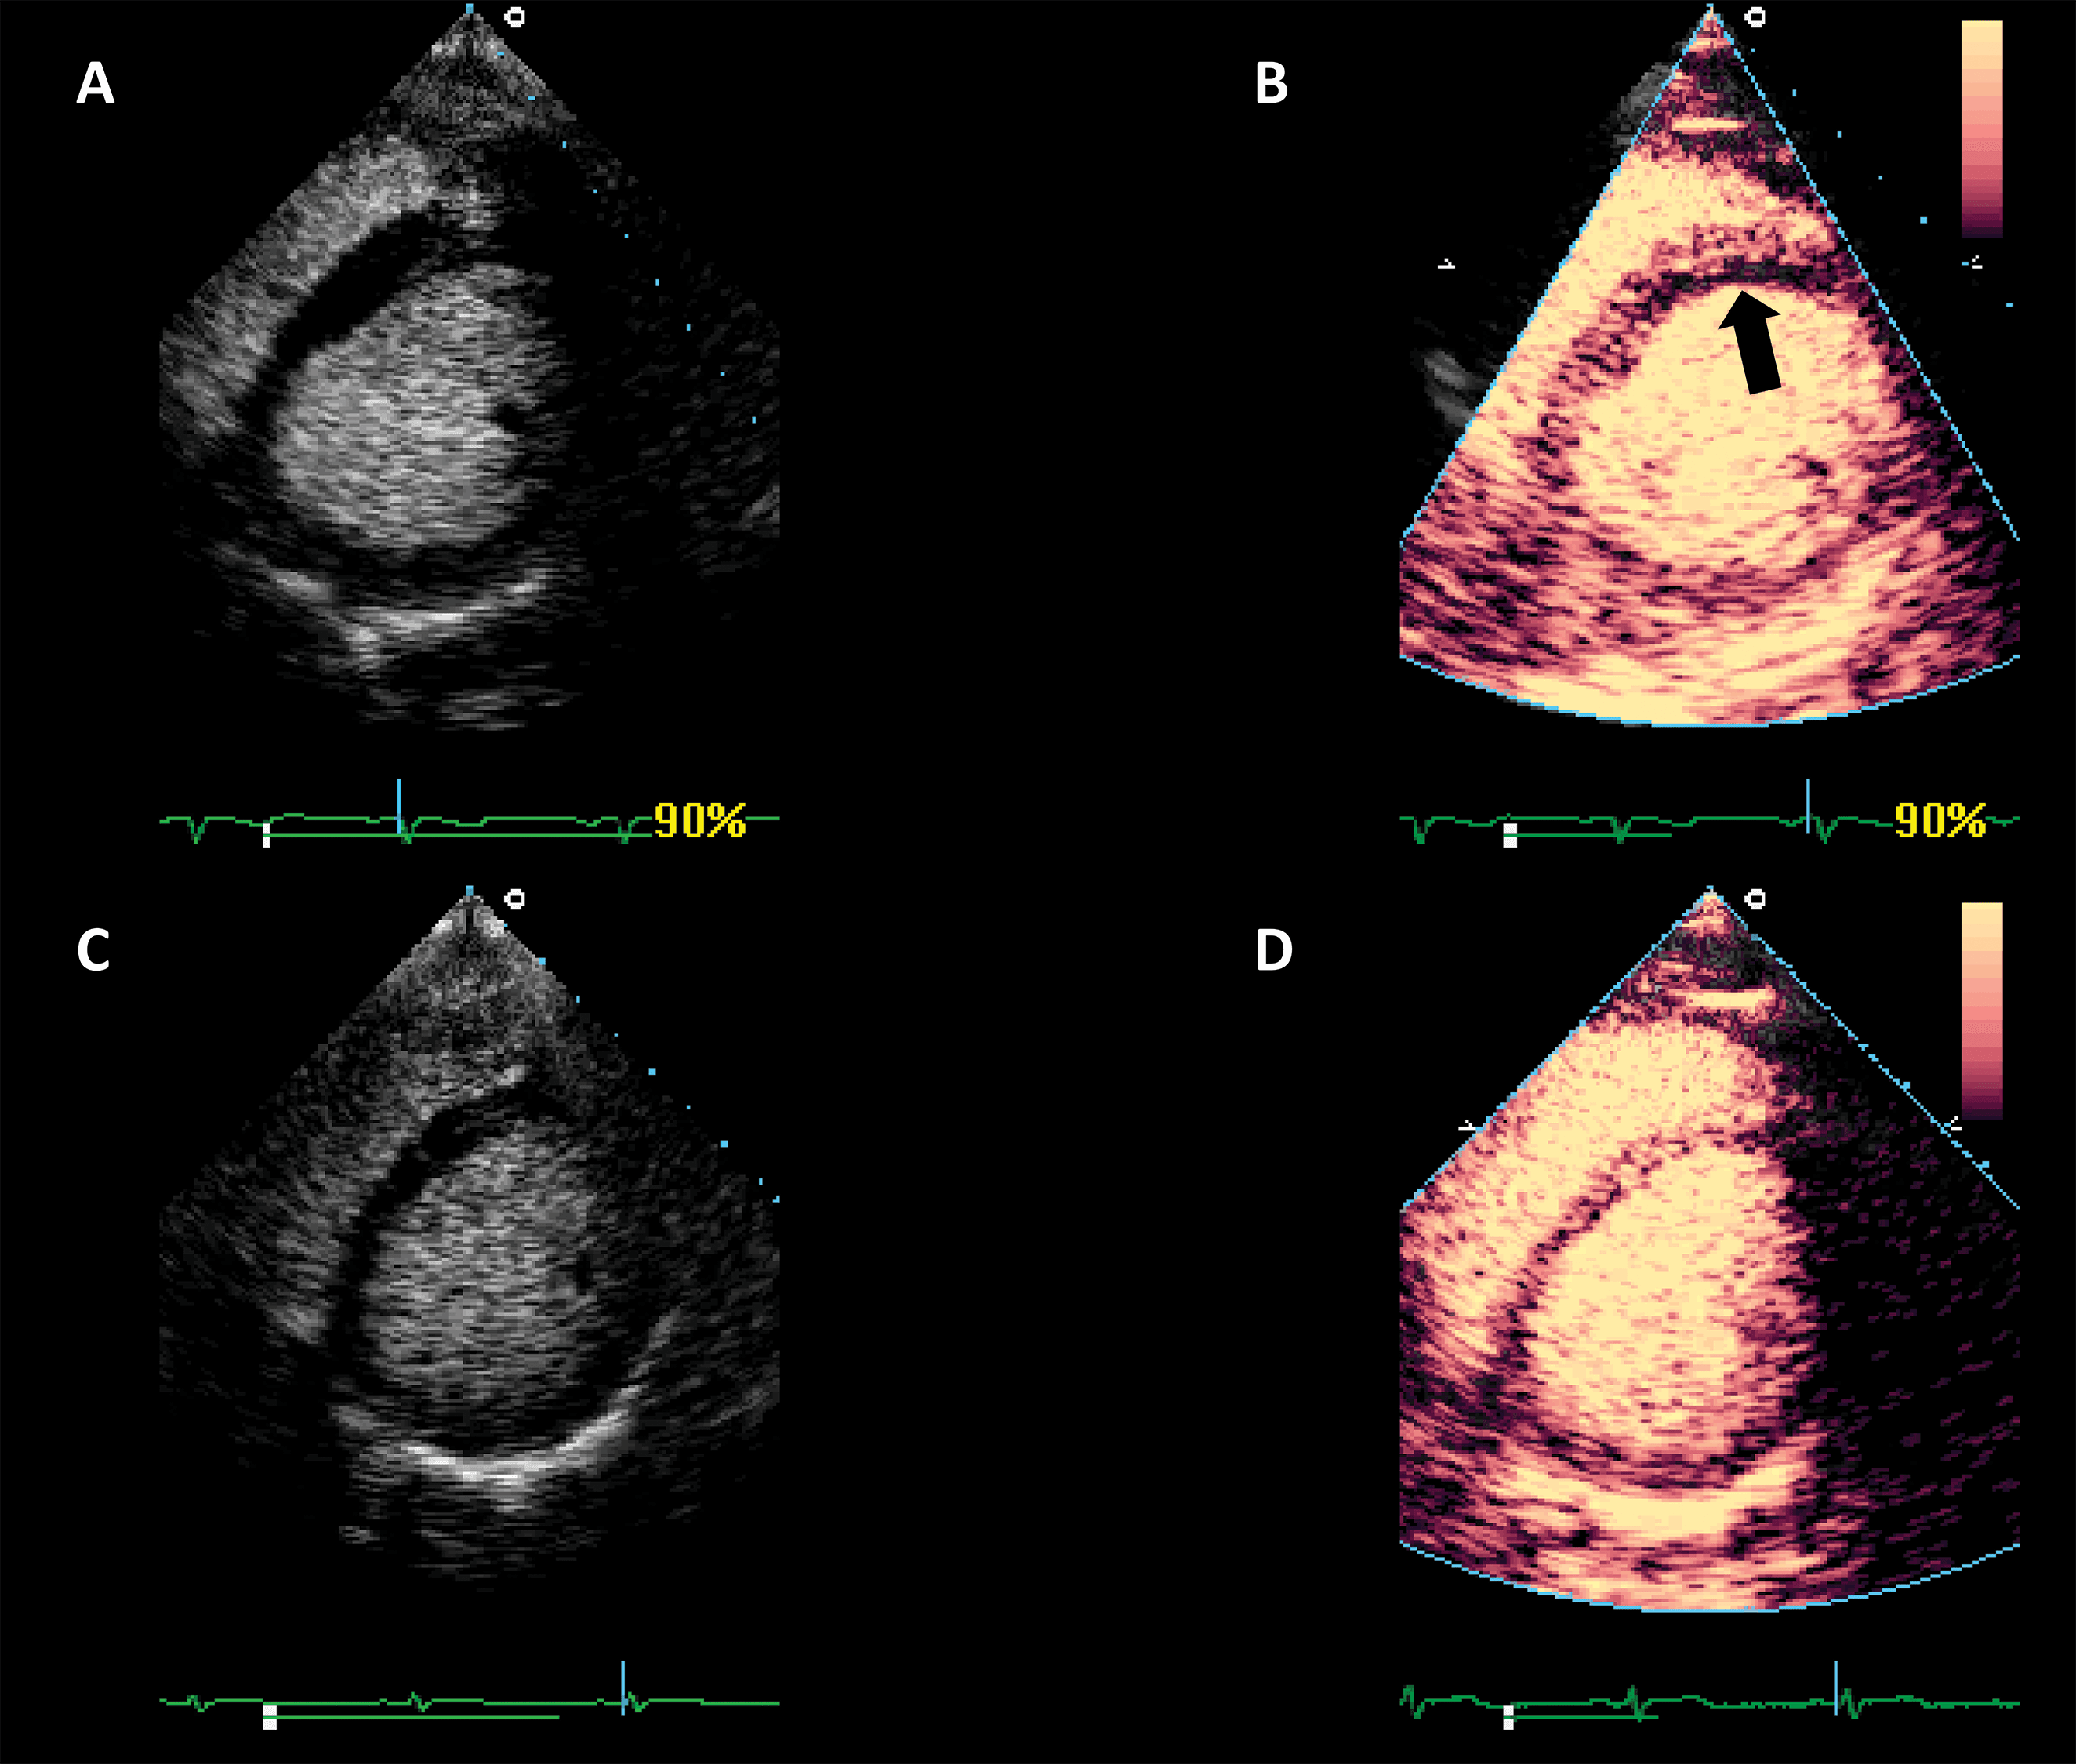

The largest body of evidence for MEE concerns the indication for LVO for enhancing the endocardial borders [10, 11, 12, 13, 14, 15]. This is achieved by using repetitive intravenous boluses of UEA, and sometimes continuous low-dose infusion. Guidelines indicate the use of LVO to enhance the endocardial borders in cases when the LV dimensions, function or regional wall motion cannot be accurately assessed using non-enhanced ultrasound [7, 14]. The general “rule of thumb” is to use microbubble UEA in cases where two or more contiguous myocardial segments are not properly visualized with non-enhanced ultrasound [13]. Of course, recent years have seen tremendous improvement in image quality for clinical ultrasound systems. But despite the introduction of harmonic imaging as a standard, some images remain non-diagnostic (Fig. 2). Moreover, harmonic imaging represented a significant leap in MEE [16, 17], leading to the present-day contrast-specific imaging modalities.

Fig. 2.Left ventricular opacification (LVO) for endocardial border delineation. Example of baseline non-enhanced echocardiography images in apical 4-chambers (A) and apical 2-chambers (B) views, where the visualization of the endocardium is suboptimal over several segments. After intravenous injection of a bolus of UEA, there is full opacification of the LV cavity, with clear delineation of the endocardium in all segments (C, D). Source: personal collection.